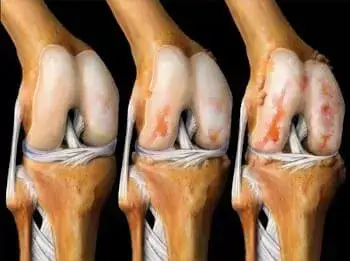

img

Efectul artrozei asupra țesutului cartilaginos al articulației genunchiului.

Din păcate, doctorul avea dreptate...După 2 luni, a fost insuportabil de dureros să mă ridic în picioare, medicamentele și analgezicele au încetat să mă ajute, deși am aruncat mulți bani pe ele, iar medicamentele mi-au distrus stomacul și ficatul - a trebuit să renunț la medicamente! A trebuit să cumpăr un scaun cu rotile și așa să mă mișc prin apartament... Doctorul a spus că în 3 ani osteoartrita distruge țesutul cartilaginos, dar văd că a început mult mai devreme, cel mai interesant lucru este că simțeam durere în articulații, și apoi într-un fel totul s-a schimbat brusc, și m-am găsit într-un scaun cu rotile, fără speranță de recuperare, după cum îmi amintesc, lacrimile se rostogoleau, și aceasta a fost cea mai groaznică perioadă din viața mea.…..